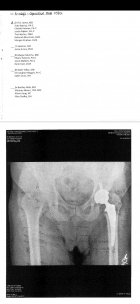

Had my hip replacement performed may 1st. Diagnosed at age 6 with Leg Perthes disease. It kills the ball part of your hip. At age 53 I'd had enough, decided it was time. I was 2 inches short in the left leg. The new hip didn't hurt too bad. The stretching of all my muscles and tendons was/is BRUTAL! Just now getting around semi decent. Lost 30 lbs in the 1st 2.5 weeks, couldn't eat anything without throwing it back up. Had me on 22 pills per day. Once I stopped them I could eat. Then, the muscle relaxer I was on started making me shake in my hands extremely bad. Plus, it made me where I couldn't talk without getting lost in the conversation, I would just lock up. Finally got off of the relaxer, it all went away. It's been a BAD deal, I was regretting it up until about 2.5 weeks ago, just started feeling better 1 day, going pretty decent since then. The picture of my ankle is from 2016, compound fracture. Same leg as my bad hip. Had about 7-8 inches of bone coming out of my leg. Wouldn't recommend. Anyway, heal up fast all you that have had something worked on, I know what you're going through. Screenshot_20240506_165445_File Viewer.jpgResized952016102095151923001.jpg20161130_152428.jpg